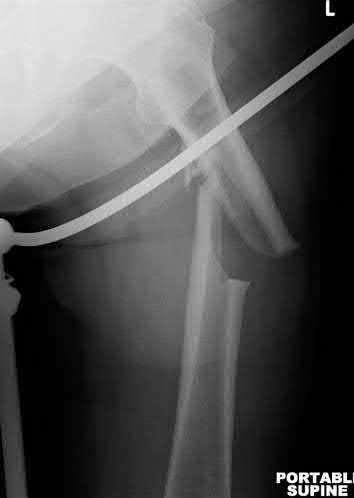

Question 1:

A 12-year-old obese boy presents with vague left thigh and knee pain. He is diagnosed with a Slipped Capital Femoral Epiphysis (SCFE) as seen in similar clinical scenarios. During percutaneous in-situ fixation, unrecognized penetration of the guide wire into the hip joint occurs. What is the most likely specific complication resulting from this technical error?

Correct Answer: Chondrolysis

Explanation:

Chondrolysis is a severe complication of SCFE characterized by rapid destruction of the articular cartilage. While it can occur idiopathically, its most established iatrogenic cause is unrecognized intra-articular hardware penetration. The 'approach-withdraw' fluoroscopic technique is required during pinning to assure pins are entirely intraosseous. Avascular necrosis (AVN) is usually due to damage to the epiphyseal blood supply (retinacular vessels) secondary to the initial displacement, forceful closed reduction, or posterosuperior pin placement.